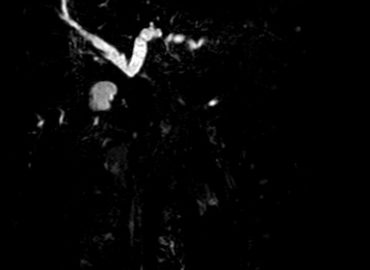

Paciente masculino de 47 años de edad acude ictérico a su control de anticoagulación oral.